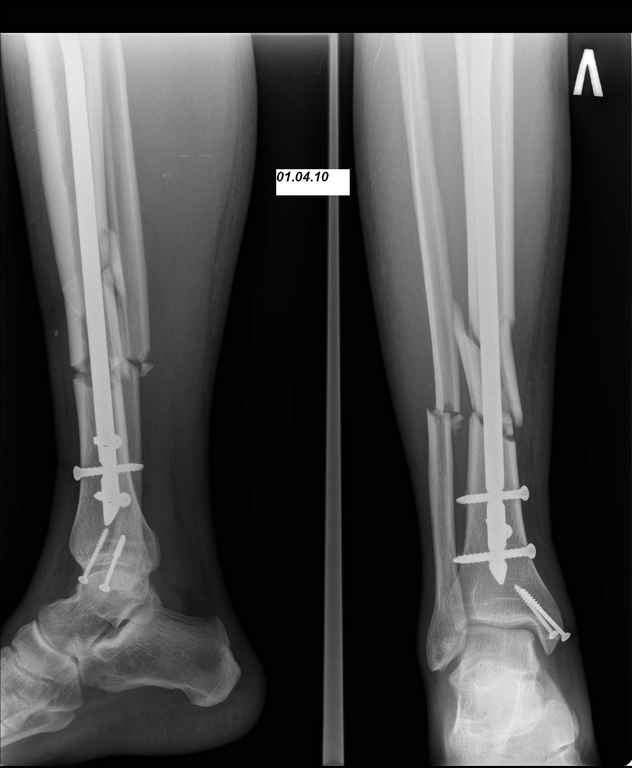

24.03.10 выполнены операции - БИОС перелома большеберцовой кости левой голени (штифт Synthes), остеосинтез перелома внутренней лодыжки левой голени винтами. Послеоперационный период протекал без осложнений. Выписан на 10 сутки. Амбулаторно не наблюдался.

07.04.10 госпитализирован с диагнозом: Нагноение парафрактурной гематомы. При поступлении отек, болезненность при пальпации, гиперемия кожи по передней поверхности, пальпаторно флюктуация в месте перелома, местное повышение температуры кожи. выполнена пункция гематомы, получено 40 мл гнойно-геморагического пунктата. Взят бак посев (S. aureus, чувствительный ко всему что у нас есть). В место флюктуации введен раствор Новокаина 1%-30 мл+Гемтамицина 2,0 мл. Сформировался свищ в месте пункции, который закрылся через 10 дней. Проводились внутрикостные инъекции антибиотика (Кламосар, полусинтетический пенициллин, бета-лактамный) в левую пяточную кость №10. Температура за период госпитализации не выше 37,2С. По анализам небольшой лейкоцитоз. Свищ закрылся, локально гиперемия, отек, местное повышение температуры регрессировали. Выписан. И опять пропал. Травмполиклинику не посещал, на контрольные осмотры к лечащему врачу не приходил.

Во первых штифт тонкий, во вторых коротккий. Не смотря на то что дистальное блокирование выполнено 3 винтами, связь с коротким дистальным отломком получиласть слабоватая если учесть активный образ жизни пациента и его "ненадежность" как выразился Александ Николаевич.

Инфекция в зоне перелома "07.04.10 (S. aureus, чувствительный ко всему что у нас есть)" - это вторичный фактор. Если бы штифт был стабильным, обострения вероятнее всего не было бы.